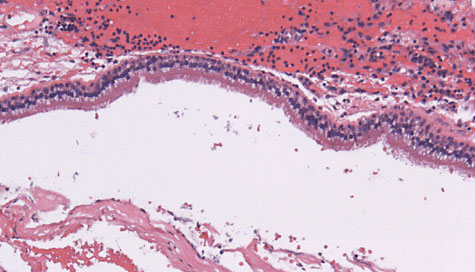

Choroid Plexus Papilloma

WHO grade I

Tumor closely resembles normal choroid plexus, except it forms a mass

- can see hydrocephalus due to CSF overproduction or obstruction, although generally behaves in a benign manner

85% seen in kids (~10 yo), intraventricular (lateral ventricles) tumor

- can occur in the 4th ventricle of adults

Micro: Benign papillary tumor

- distinguish from normal choroid plexus by closely inspecting the lining epithelium

-- normal choroid plexus is lined by taller columnar epithlium which is smooth, but lacks the undulating surface of normal choroid plexus epithelium which is smooth and lacks the undulating surface of normal choroid plexus

- there should be no signoficant atypia and mits should be absent or rare

DDx: carcinoma mets, myxopapillary ependymoma, papillary ependymoma (>1 cell layer), papillary meningioma (no mucin, solid c foci of whorled cells)

IHC: (+) CAM5.2 (94%), transthyretin (89%), GFAP, Kir71

- usually negative p53 and CK20

- CAM5.2 good bc ventricle only epithelial structure in brain, which can stain c CAM5.2